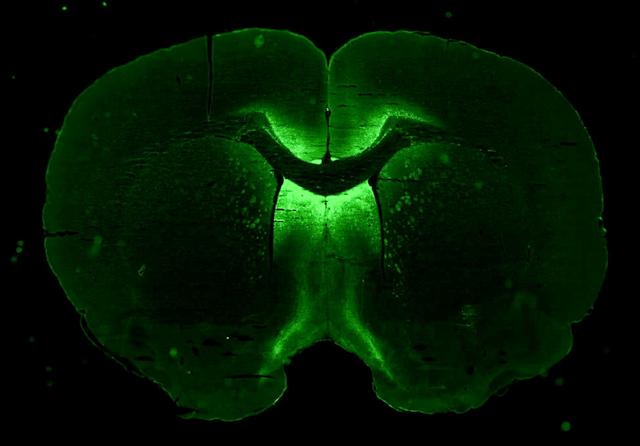

Preflight Imagery for the Neuronix Investigation

jsc2023e026250

JSC | 2023-04-28

jsc2023e026249